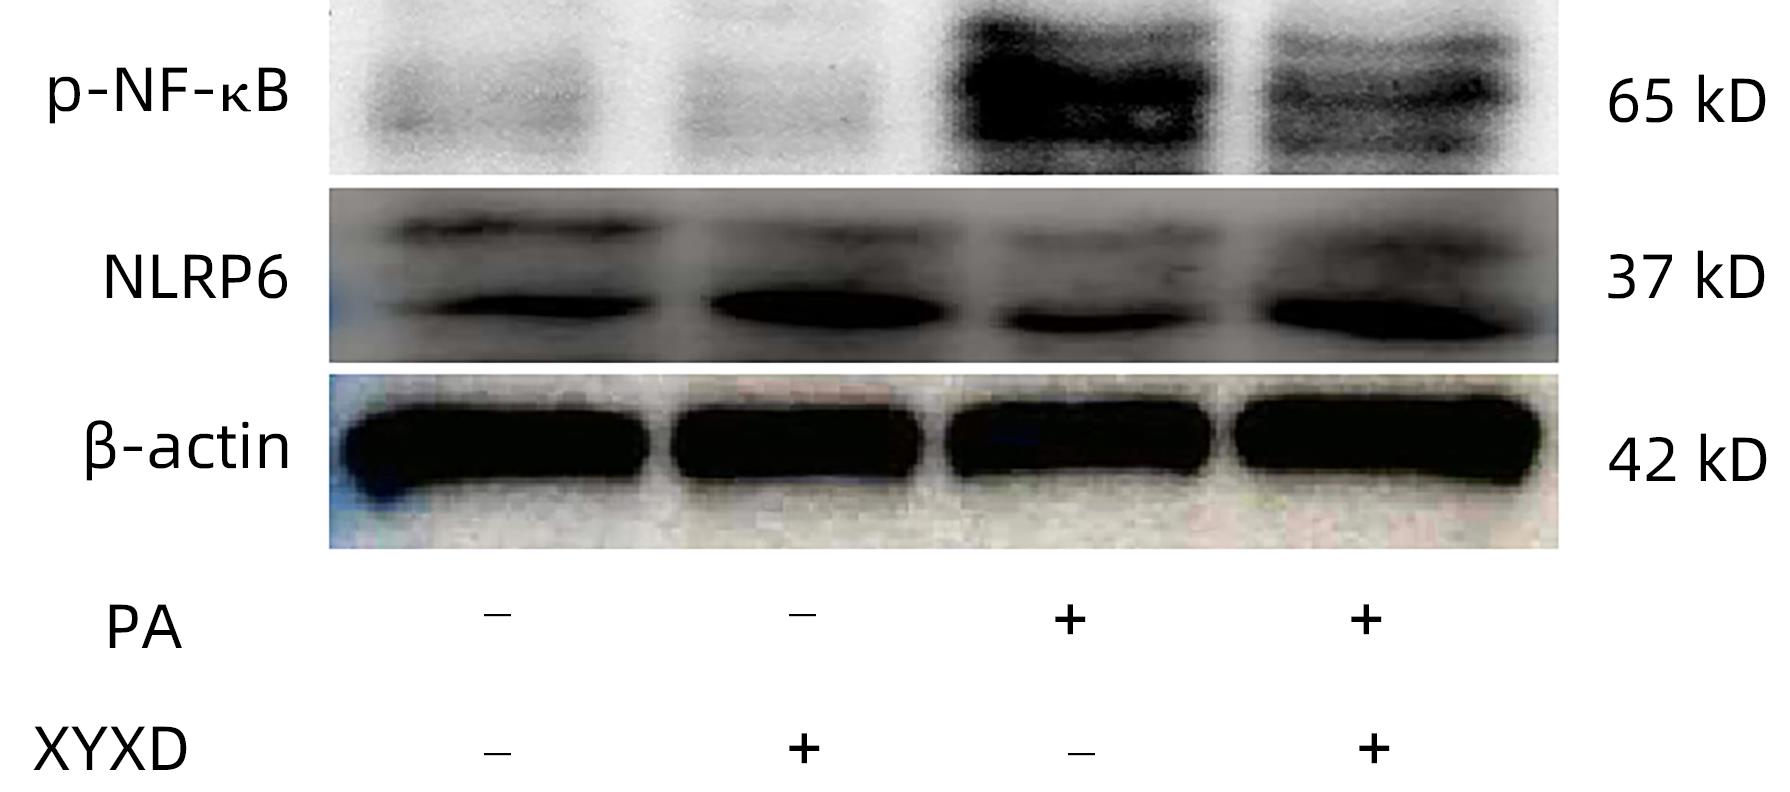

下瘀血汤对高脂饮食诱导的非酒精性脂肪性肝病小鼠模型的治疗作用及机制

侯林圻, 王知意, 赵鑫, 张洁, 马文婷, 刘旭凌, 张玮, 陶乐, 刘成, 吴柳

2024, 40(4): 712-719. DOI: 10.12449/JCH240412

摘要(1540) HTML (452) PDF (2184KB)(93)

摘要:

目的  探讨下瘀血汤调控核苷酸结合寡聚化结构域样受体含pyrin结构域蛋白6(NLRP6)抑制高脂饮食(HFD)诱导的小鼠非酒精性脂肪性肝病(NAFLD)的作用机制。  方法  15只雄性C57BL/6小鼠随机分为低脂饮食(LFD)组、HFD组和下瘀血汤-HFD(XYXD)组,每组各5只。测量肝功能指标ALT和AST、血脂代谢指标TG、TC水平;肝组织经过HE染色、油红O染色,观察小鼠组织形态、脂滴沉积;实时荧光定量PCR检测肝组织中炎症因子TNF-α、IL-1β、IL-6及NLRP6表达水平;Western Blot检测NLRP6、NF-κB和NF-κB p65蛋白水平;免疫组化检测NLRP6和CD68表达。棕榈酸(PA)、脂多糖(LPS)和下瘀血汤含药血清处理鼠Raw264.7细胞,检测炎症情况。计量资料多组间比较采用单因素方差分析,进一步两两比较采用LSD-t检验。  结果  与LFD组比较,HFD组血清ALT、AST和TC、TG水平显著升高(P值均<0.05)。肝组织病理学显示,HFD组肝脂肪变性明显,NAS评分显著升高(P<0.05);实时荧光定量PCR结果显示,IL-1β、IL-18等炎症相关因子显著升高,NLRP6表达显著下调(P值均<0.05)。免疫组化显示NLRP6表达与巨噬细胞标志物CD68重合。Western Blot显示,NLRP6表达下调后,磷酸化的NF-κB p65(p-NF-κB p65)显著上调(P<0.05)。与HFD组相比,下瘀血汤可有效改善HFD小鼠的肝脏炎症,上调NLRP6的表达,下调p-NF-κB p65(P<0.05)。PA处理Raw264.7细胞后下调NLRP6,促进炎症进展(P<0.05);下瘀血汤处理可上调NLRP6,抑制炎症和NF-κB(P<0.05)。  结论  下瘀血汤可显著改善HFD诱导NAFLD小鼠模型的肝脂肪变性和炎症,调控NLRP6/NF-κB减轻巨噬细胞活化可能是其作用机制之一。